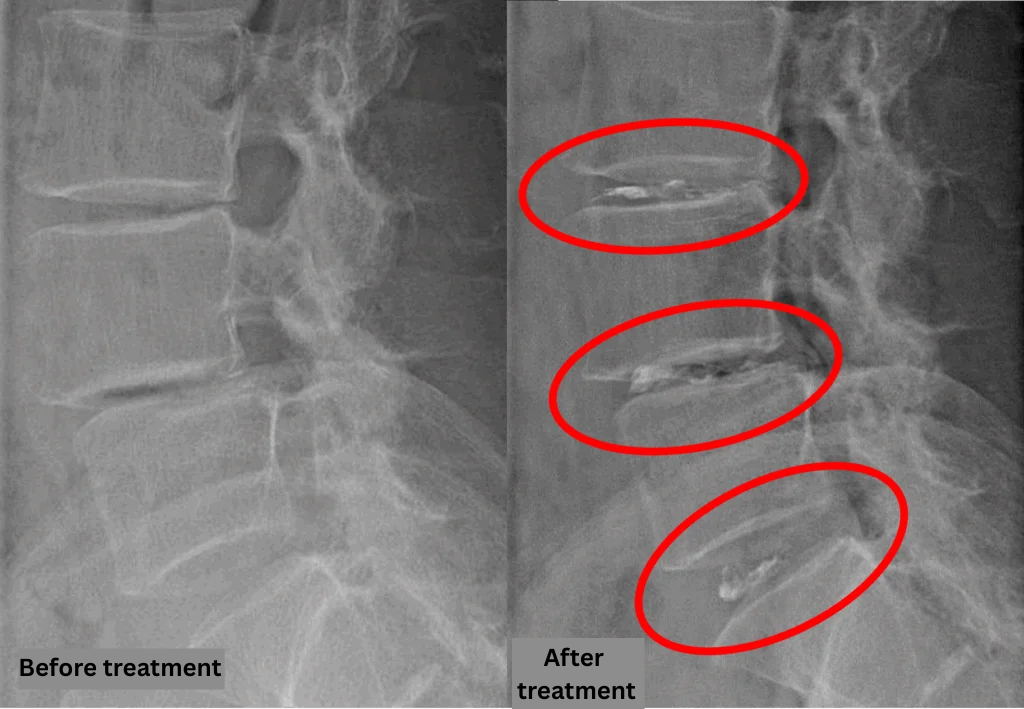

After consulting with the patient, the Cellgel Method was performed on L3/4, 4/5 and 5/s.

The treatment was performed by our administrative director, Dr. Kotera.

The treatment took about 25 minutes.

After resting in the recovery room, the patient was able to walk home unaided.